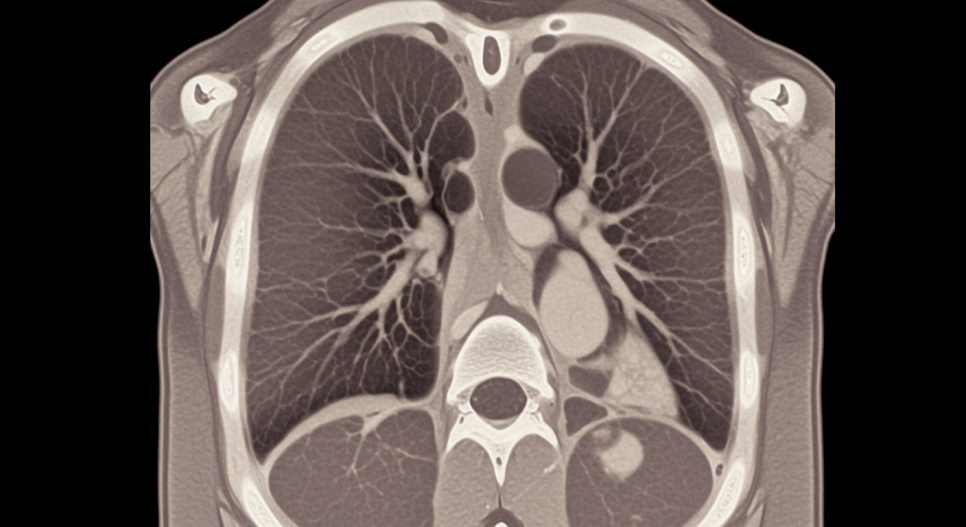

- 간질성 폐 질환 (Interstitial Lung Disease, ILD)

가장 흔한 사망 원인

초기 무증상이나, 점차 진행되는 호흡곤란, 기침

HRCT에서 NSIP > UIP, COP 패턴

A3. 근효소 수치(CK, aldolase) 혈액검사, 폐기능 검사(DLCO 포함), 고해상도 흉부 CT로 간질성 폐질환 여부를 확인해야 합니다. 근력 약화가 있으면 근전도(EMG)와 필요시 근육 생검도 고려됩니다. 조기 발견이 폐 섬유화 진행을 늦추는 데 매우 중요합니다.